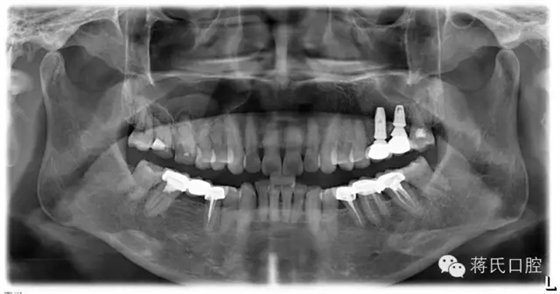

8.種植后全景片

12.修復后全景片